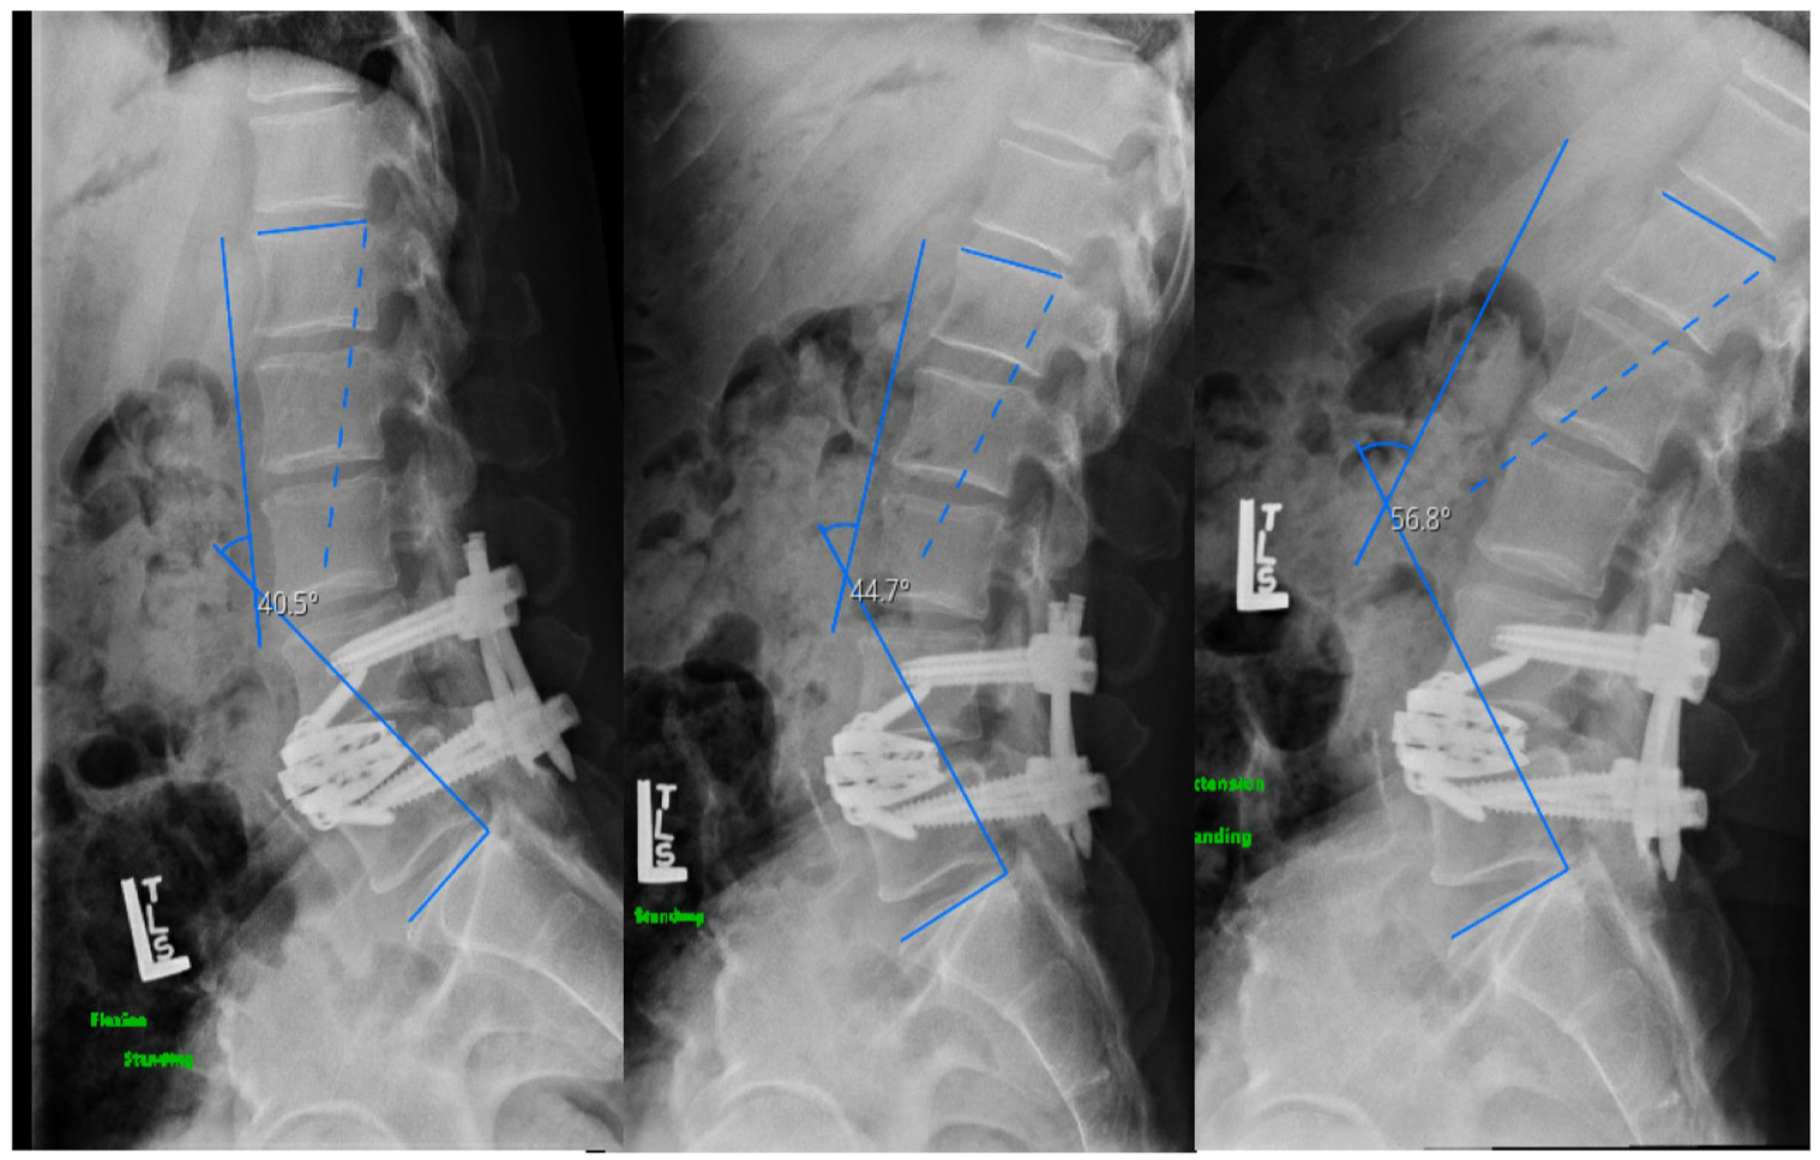

2.4.1. Case I